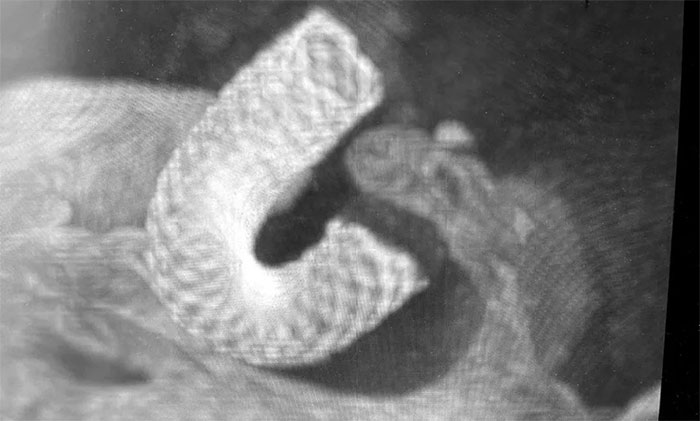

經(jīng)充分完善術(shù)前準備,席剛明教授在麻醉科和介入手術(shù)室緊密配合下,開展右頸內(nèi)動脈眼動脈段動脈瘤血流導(dǎo)向裝置(Pipeline)置入術(shù)。手術(shù)歷時兩個小時,順利“拆除”了埋在患者腦子里的“不定時炸彈”。

▲ 造影顯示血流導(dǎo)向裝置貼壁良好